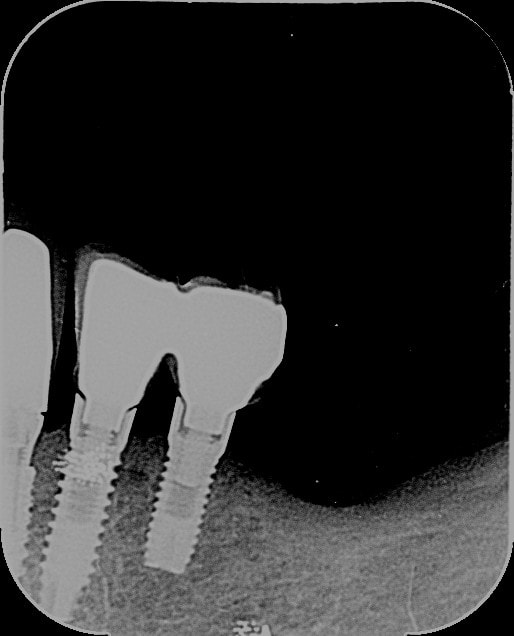

avis aux boss de l'identification implantaire, pouvez-vous me dire quelle est la marque de ces implants? mes recherches restent infructueuses.

amha du leader italia ou similaire....

on s'en fout un peu, c'est de l'hexagone classique type Zimmer/MIS/biohorizon, etc...